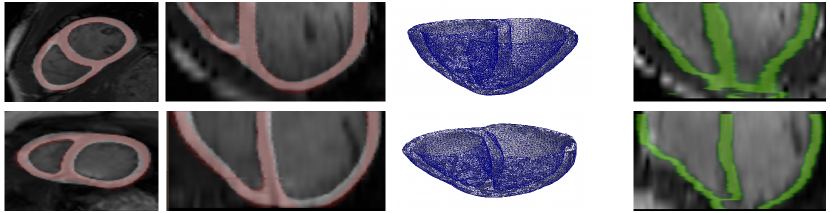

The method is tested on the end-diastole (the only instant where ground truth is available) of testing cases. It takes about 3s to segment a volume using GPU. The output probabilities are binarized to obtain myocardium/background segmentation taking 0.5 as threshold. We use the Dice index to measure performance. The 3D Dice indices (considering all pixels of all slices below base) are 0.7851 for v1 and 0.7817 for v2. The predicted masks and the ground-truth (axial and coronal views) as well as the BV meshes generated directly from the predicted masks using CGAL 111http://www.cgal.org are presented in the left part of Fig. 3. In the right part of Fig. 3, 2D Dice indices for both subjects change smoothly across slices, confirming the spatial consistency of our method.

For comparison, if we use the initialization network to segment all the slices independently without propagation, the method not only loses the spatial consistency but also fails completely on the slices near apex (the middle part of Fig. 3). Our propagation method therefore appears crucial to maintain spatial consistency and reach accurate results even on the most difficult slices.